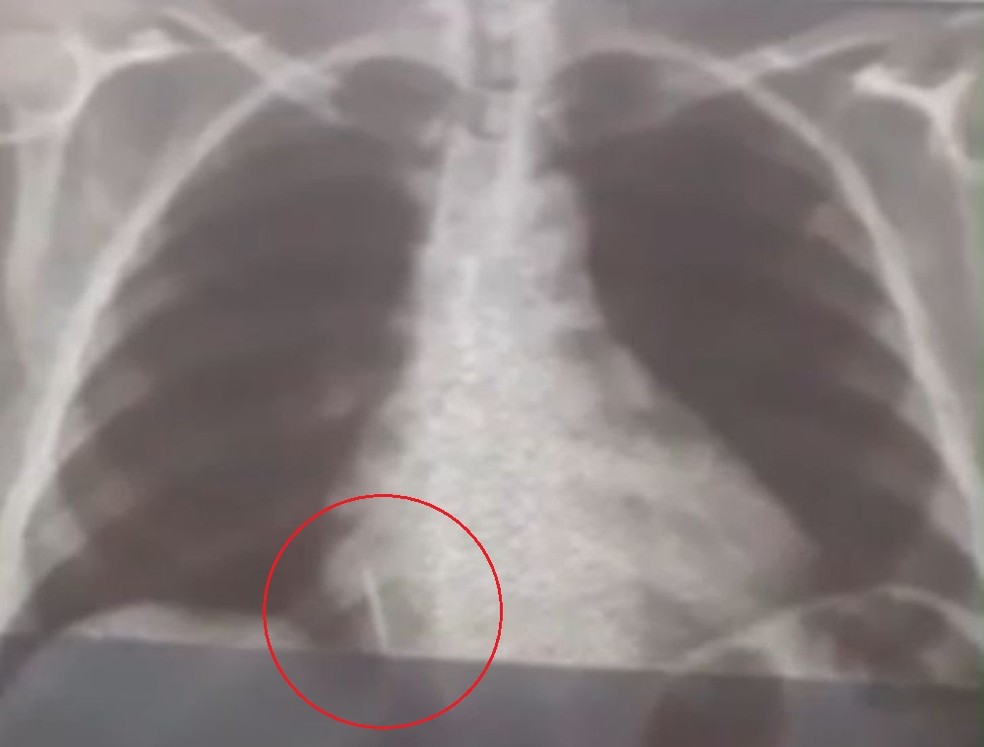

O caso aconteceu no dia 26 de julho, mas o material ainda permanece alojado no pulmão da paciente. Para o G1, o filho da mulher afirmou que ela sente dores e não consegue comer direito.